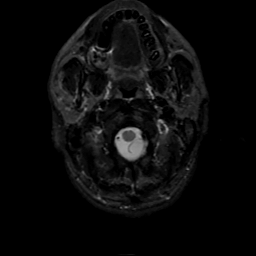

MR Study #7, March 24, 1991 -- Slice #1